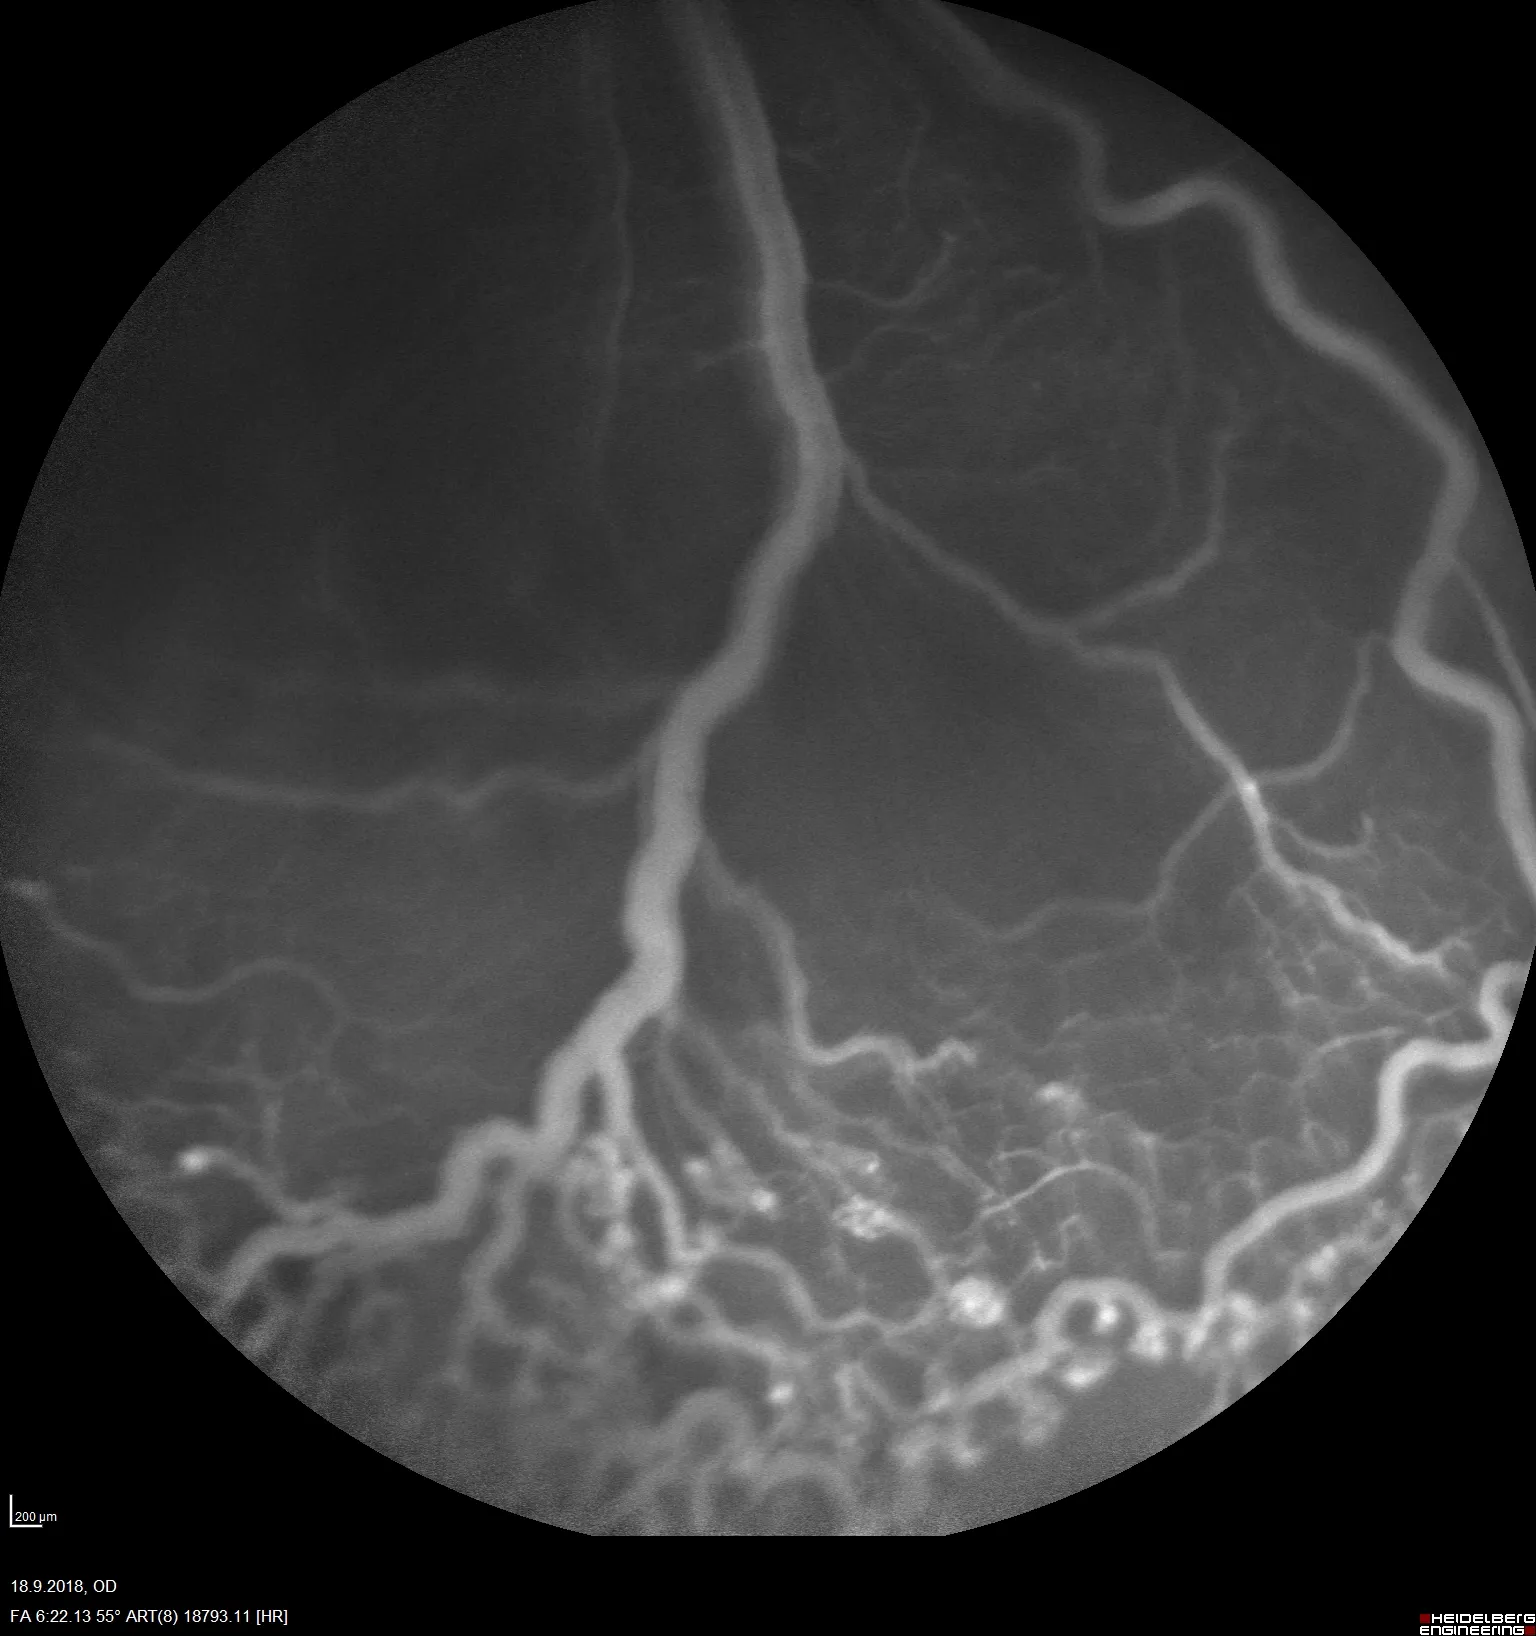

At Experimentica, we have implemented and validated both mouse and rat OIR models with a clinically relevant reference compound making them ideal for screening anti-angiogenic drug candidates. Our capabilities include morphological analysis of retinal vasculature from flat mounts, combined with in vivo imaging, such as fluorescein angiography (FA) and flash electroretinography (ERG).

In vivo imaging (FA, rat model)

Non-invasive in vivo imaging techniques and high-quality tissue samples to detect efficacy